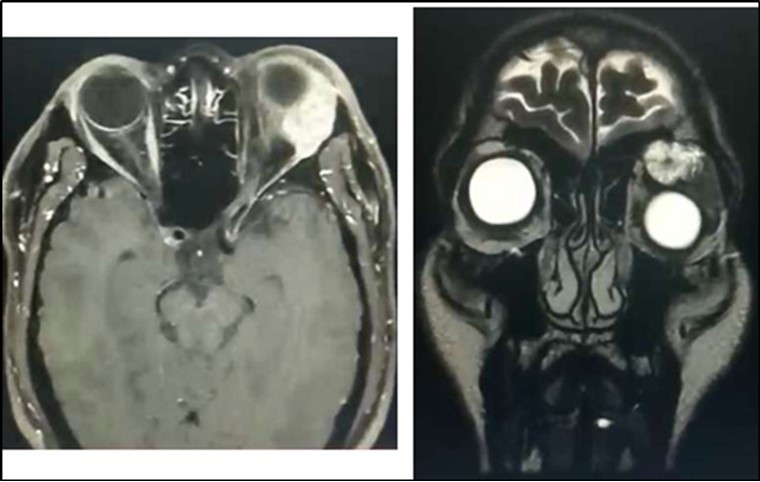

Orbital MRI showed a 2.6 x 2.9 x 3.2 cm (cc x w x ap) heterogeneously enhancing mass seen in the extraconal space (superolateral aspect) likely arising from the left lacrimal gland (Figure 2). The lesion exhibits mixed (predominantly hyperintense T2 wave and predominantly intermediate T1W) signals. Mass effect was noted compressing the retrobulbar fat with resultant medial displacement of the optic nerve, inferior displacement and anterior protrusion of the globe. The mass abuts the superior rectus, levator palpebrae superioris and lateral rectus muscle.

Figure 2.Orbital MRI showing an enhancing lacrimal gland mass (Axial & Coronal Views), left